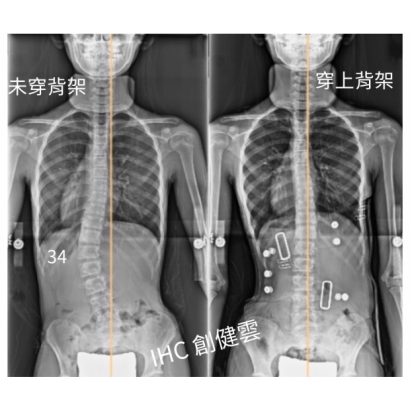

10歲脊椎側彎女孩,腰彎34度